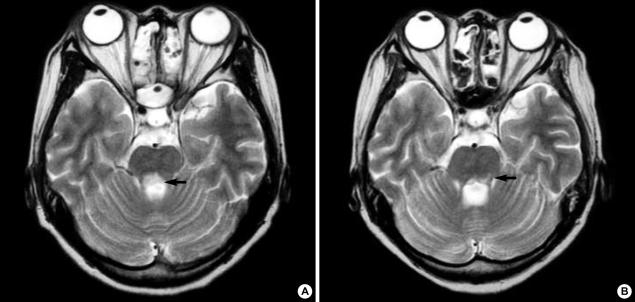

Transverse myelitis (TM) extending from midbrain to the entire spinal cord accompanied by internuclear ophthalmoplegia is extremely rare but cause serious central nervous system complications in patients with systemic lupus erythematosus. We report a case of a 28-yr-old woman with TM extending from the midbrain to the conus medullaris longitudinally and internuclear ophthalmoplegia associated with systemic lupus erythematosus. Her neurological symptoms had an abrupt catastrophic onset and rapidly progressed to respiratory failure within 24 hr. Bilateral internuclear ophthalmoplegia was also followed by TM. Brain MR images showed definite brainstem lesions, which were deeply associated with internuclear ophthalmoplegia, and diffuse signal changes in the whole spinal cord, medulla, pons and midbrain. Clinical improvement of her ophthalmoplegia and of neurological dysfunction of the upper extremities was noted after prompt and aggressive treatment with intravenous pulsed methylprednisolone and cyclophosphamide. However, the neurological dysfunction of the lower limbs and bladder and colon paralysis were almost unchanged until six months passed.

横贯性脊髓炎(TM)从脑干延伸至整个脊髓并伴有核间性眼肌麻痹极为罕见,但会在系统性红斑狼疮患者中引发严重的中枢神经系统并发症。我们报告一例28岁女性,其TM纵向从脑干延伸至脊髓圆锥,且伴有与系统性红斑狼疮相关的核间性眼肌麻痹。她的神经症状呈突发灾难性发作,并在24小时内迅速进展为呼吸衰竭。双侧核间性眼肌麻痹也先于TM出现。脑部磁共振成像显示明确的脑干病变,与核间性眼肌麻痹密切相关,以及整个脊髓、延髓、脑桥和中脑的弥漫性信号改变。在静脉注射脉冲甲基强的松龙和环磷酰胺进行迅速且积极的治疗后,她的眼肌麻痹和上肢神经功能障碍有了临床改善。然而,直到六个月过去,下肢神经功能障碍以及膀胱和结肠麻痹几乎没有变化。